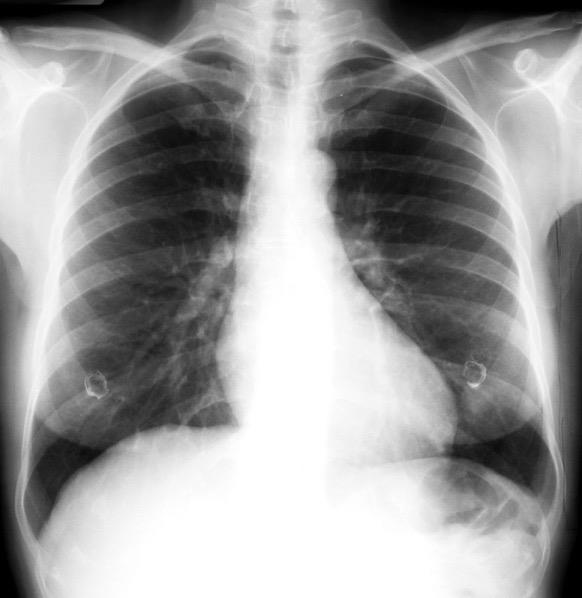

Radiografía AP en politraumatizado con enfisema subcutáneo severo.

Kumar H M,et al. Ginkgo leaf sign and subcutaneous emphysema.BMJCase Rep .2018